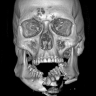

Полтора месяца назад в поселке Амгу Тернейского района 70-летнюю женщину покусал алабай — не бездомный, а хозяйский. Пес напал, когда пенсионерка была в гостях, и оставил после себя страшные рвано-укушенные раны на голове, лице и руке. Сейчас результат работы медиков — налицо: челюстно-лицевые хирурги Краевой клинической больницы № 2 восстановили женщине лицо, сообщает PRIMPRESS со ссылкой на пресс-службу больницы.

«Мы провели первичную хирургическую обработку множественных ран с элементами пластической и реконструктивной хирургии. Самым сложным участком оказалось ухо — его пришлось буквально собирать как пазл из десятка лоскутов кожи с хрящами. Вмешательство длилось около 4 часов, но нам удалось сохранить подвижность и мимику лица», — рассказал заведующий отделением челюстно-лицевой хирургии Алексей Романчук.

На прошлой неделе пациентка приехала на плановый осмотр — и, как признаются врачи, результат работы впечатляет: о нападении собаки напоминают только небольшие рубцы.